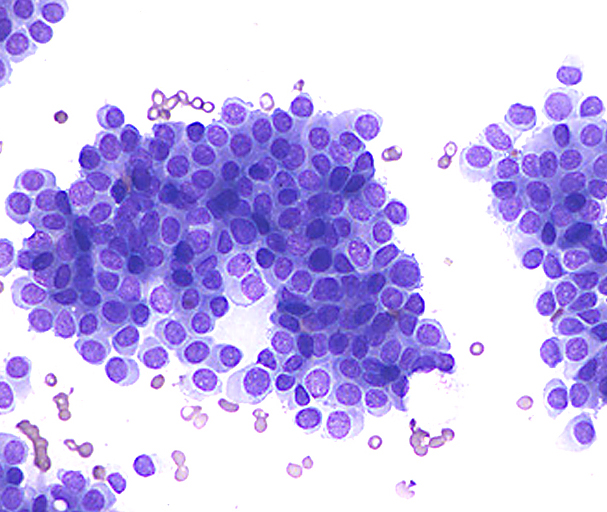

Cytology description

- Can use cellular pleomorphism, nuclear size, nuclear margin, nucleoli, lack of naked nuclei, cellular dyscohesion and mitoses in addition to necrosis to assess cytologic tumor grade, which correlates with histologic grade (Diagn Cytopathol 2003;29:185)

Cytology images